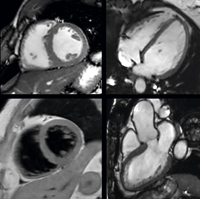

Ingeniaで撮影した心臓のシネおよび

Black Bloodイメージング |